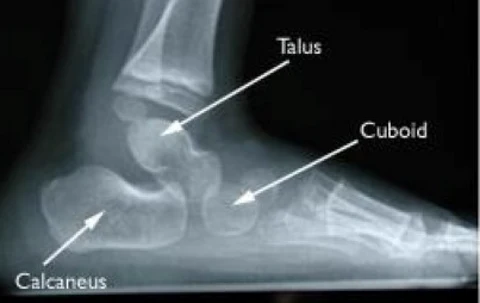

造成扁平足的原因很多,其中遺傳確實扮演著重要角色,因為有些人生來足弓骨就下垂,從未發展出正常的足弓。在扁平足的情況中,距骨(Talus)通常過度活動。如果將腳比作一座石橋,那麼距骨就像是橋中央的那塊關鍵石頭;如果我們把這塊石頭拔掉,整座橋就會坍塌。當這塊骨頭過度活動時,人在腳跟著地時,它會向前滑動,導致中足部解鎖,從而使足弓塌陷。我們可以將這種成因視為直接且局部的影響。